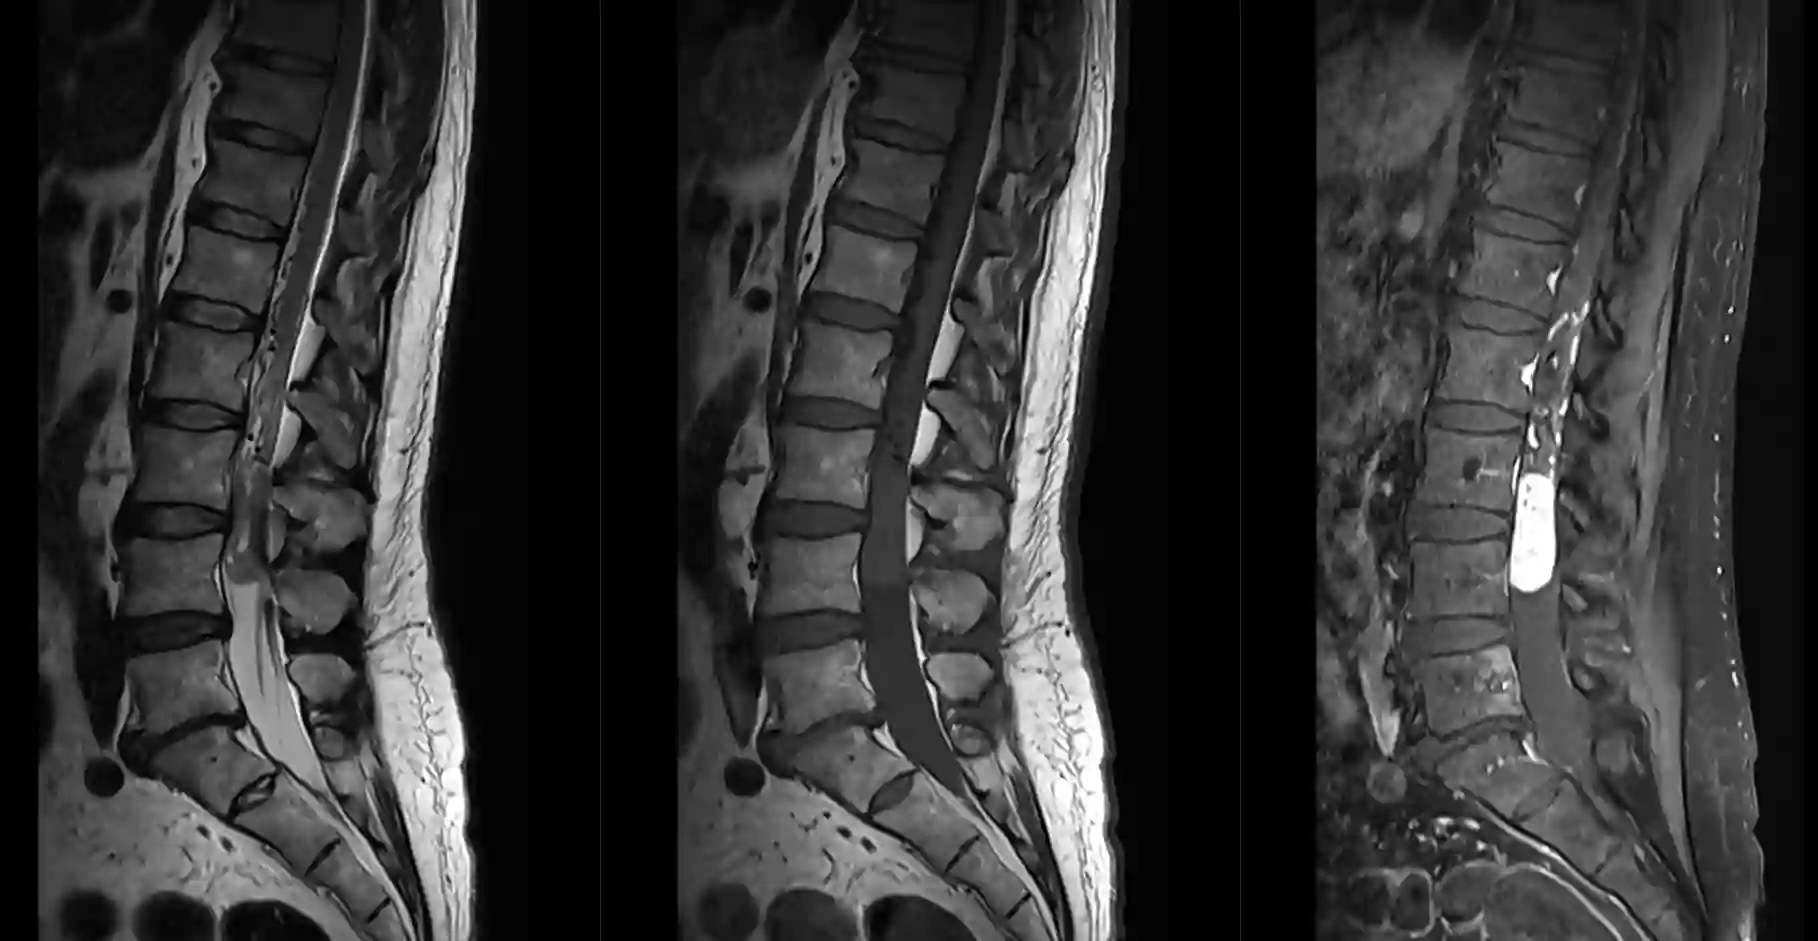

Paragangliom im Bereich der lumbalen Wirbelsäule.

lumbales Paragangliom MRI